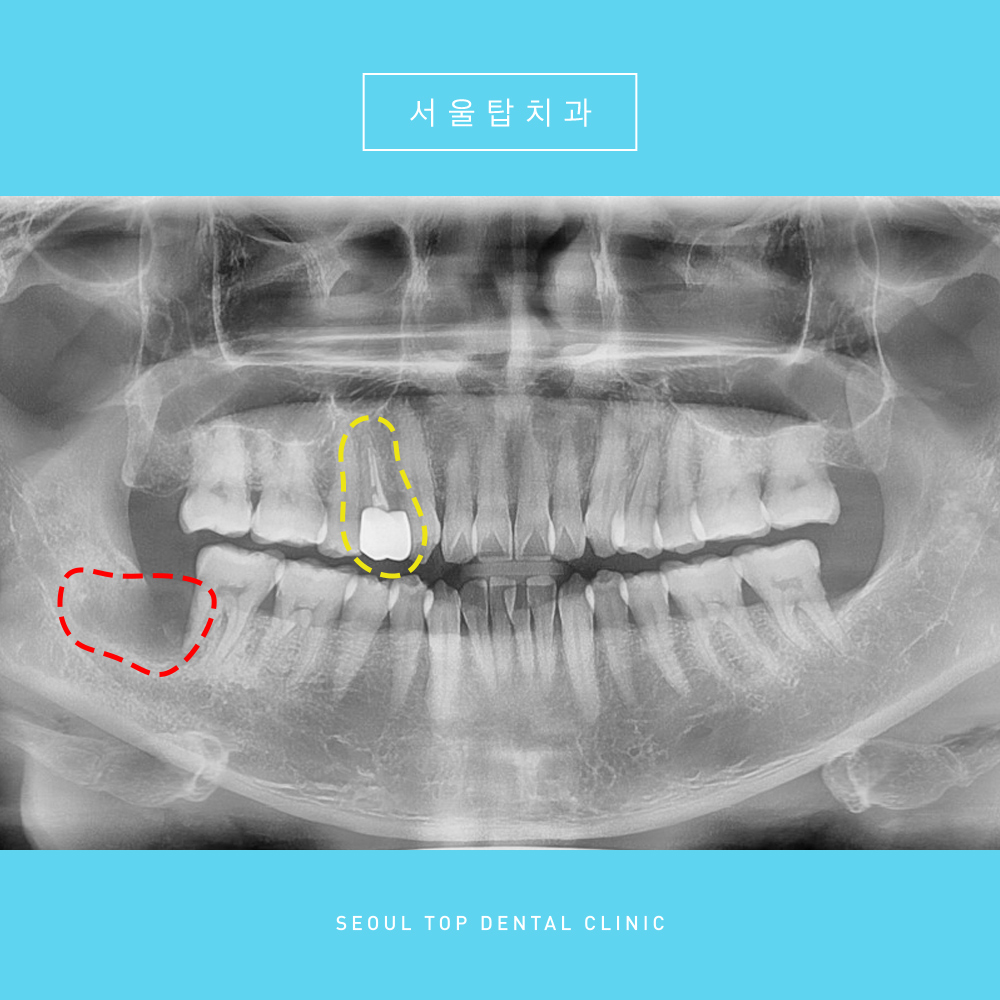

그리고 처음 내원하였을때 사진을 보시면,

충치 뿐만 아니라 사랑니로 인한

구강 내 문제점도 확인할 수 있었는데요.

오른쪽 아래 매복 사랑니로 인해,

바로 앞의 두번째 큰 어금니의 원심과 뺨측

골소실이 심한 상태였습니다.

충치치료 및 사랑니 발치를 모두 마무리 한 사진입니다. 👍

오른쪽 위의 첫번째 작은 어금니는

신경치료 및 크라운 치료를 마무리 한 것을

확인하실 수 있으며,

오른쪽 아래 사랑니는

뿌리 끝까지 깨끗하게 발치 된 모습을 보실 수 있습니다.

위 파노라마 사진은 사랑니발치 후

약 1주일이 지나고 실밥을 제거할 때

촬영한 사진인데요.